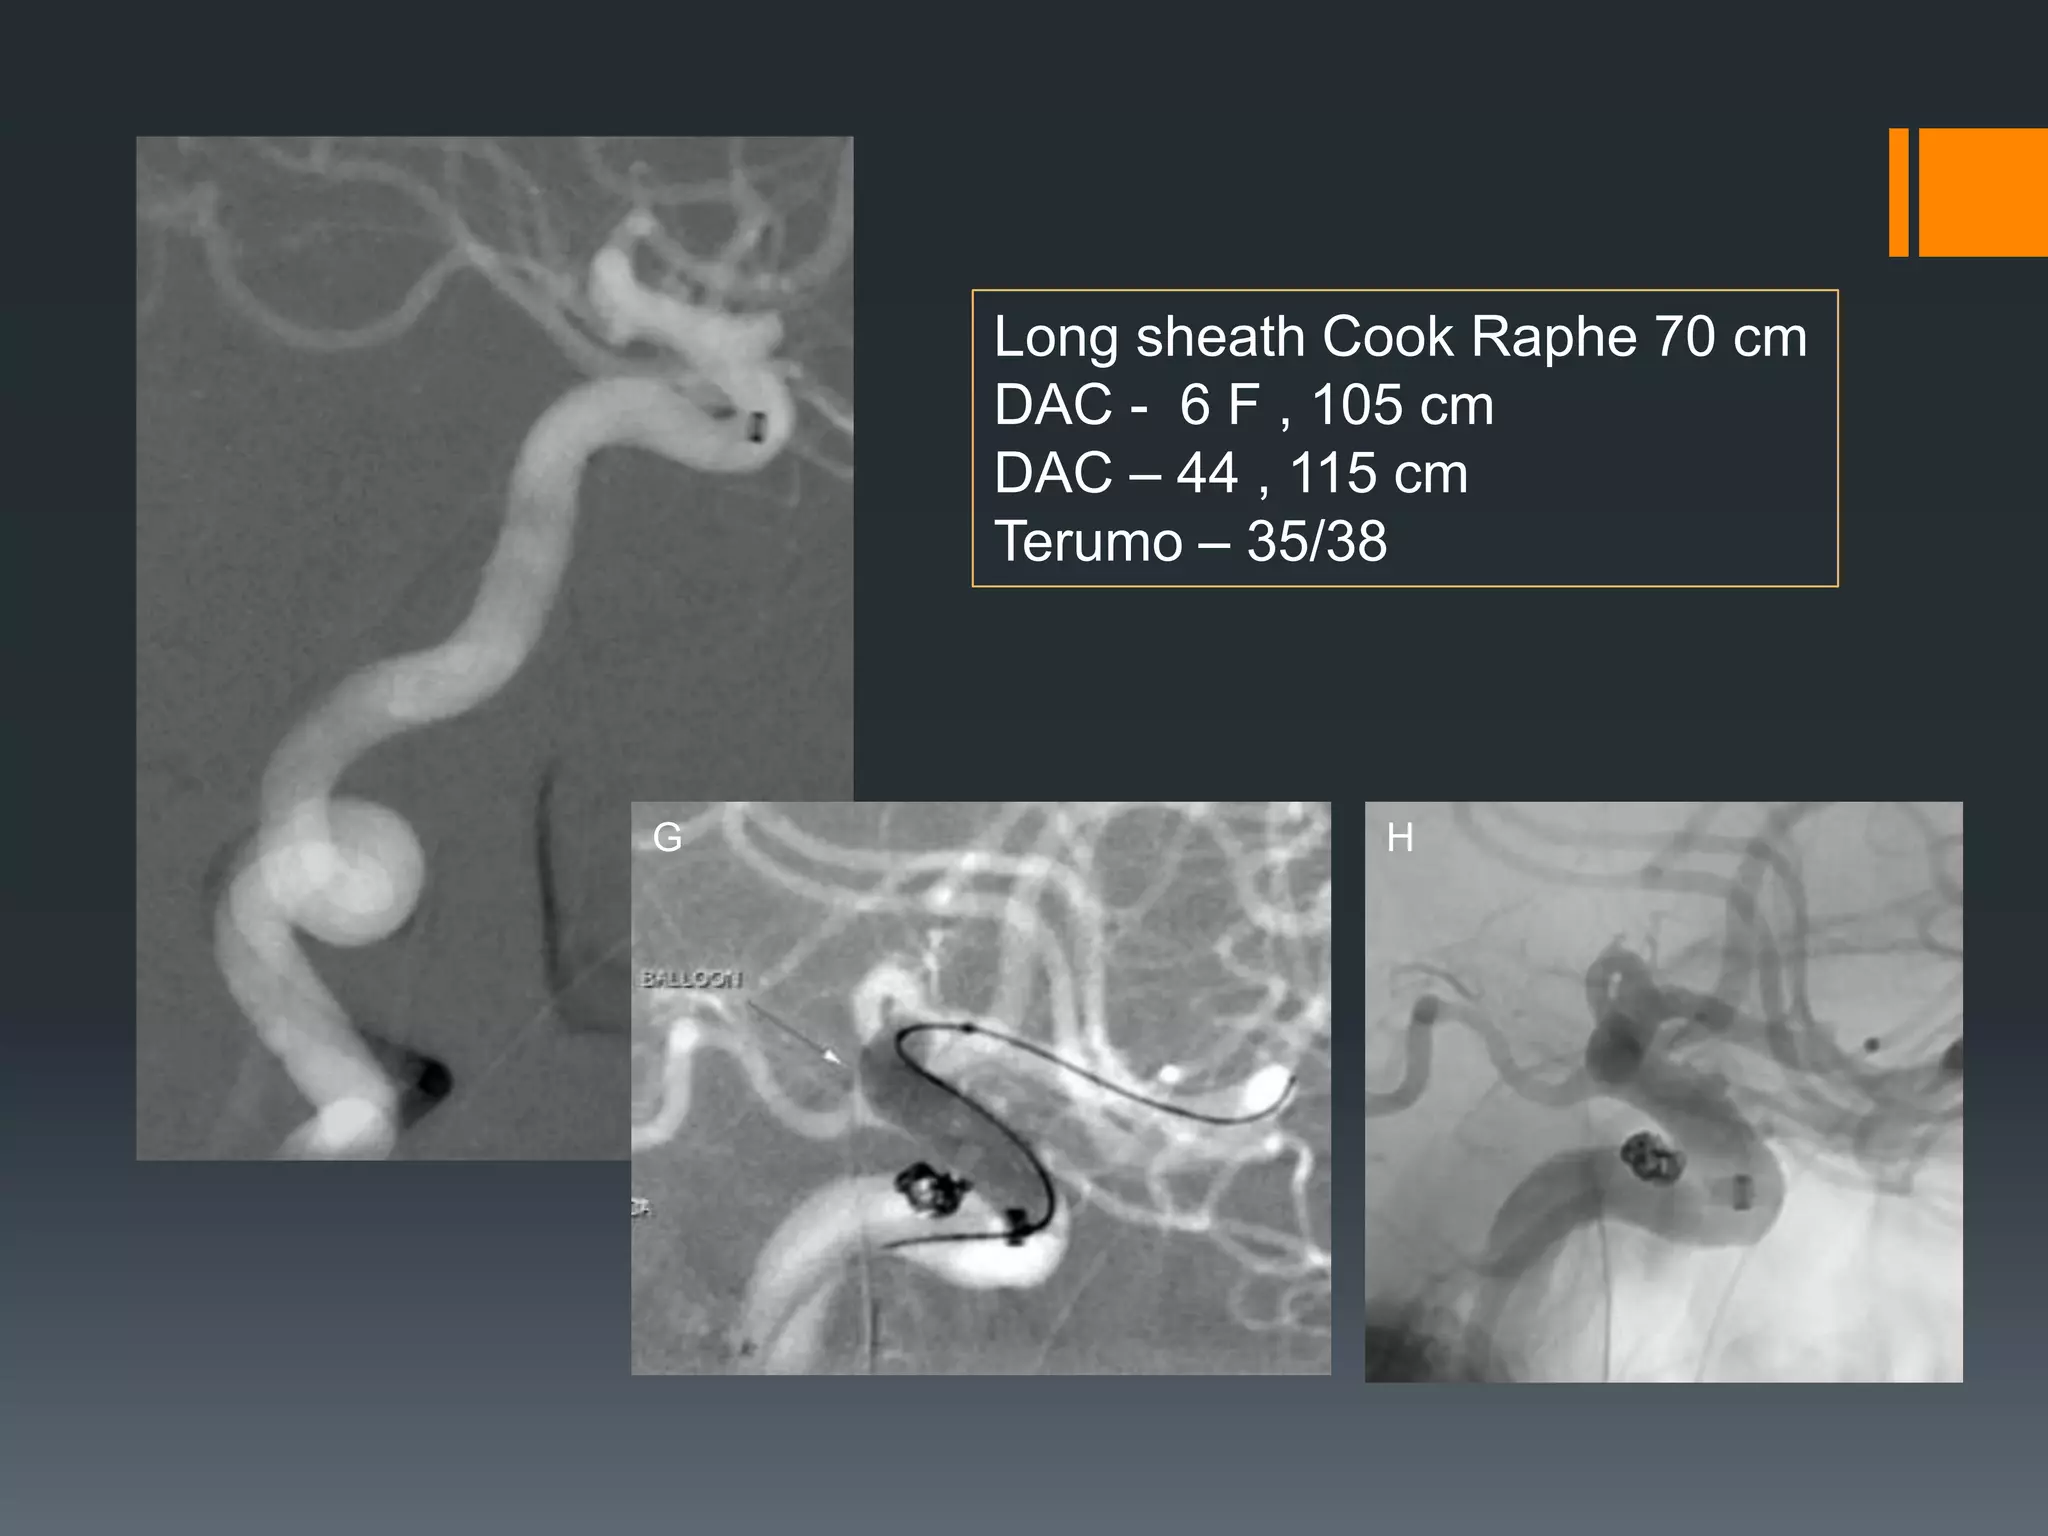

This document discusses tricks and techniques for difficult cannulations during neurointerventional procedures. It outlines strategies for accessing the aortic arch, internal carotid artery (ICA), and areas distal to aneurysms. Long sheaths, distal access catheters, and co-axial techniques are presented as options that have improved cannulation success. Guidance on sheath and catheter selection is provided for different vessel paths. The importance of catheter placement as high as possible in the ICA is emphasized. Reverse curve cannulations are also mentioned. Overall, the document stresses that careful cannulation is critical for procedural success and different strategies may be needed depending on the vessel target.